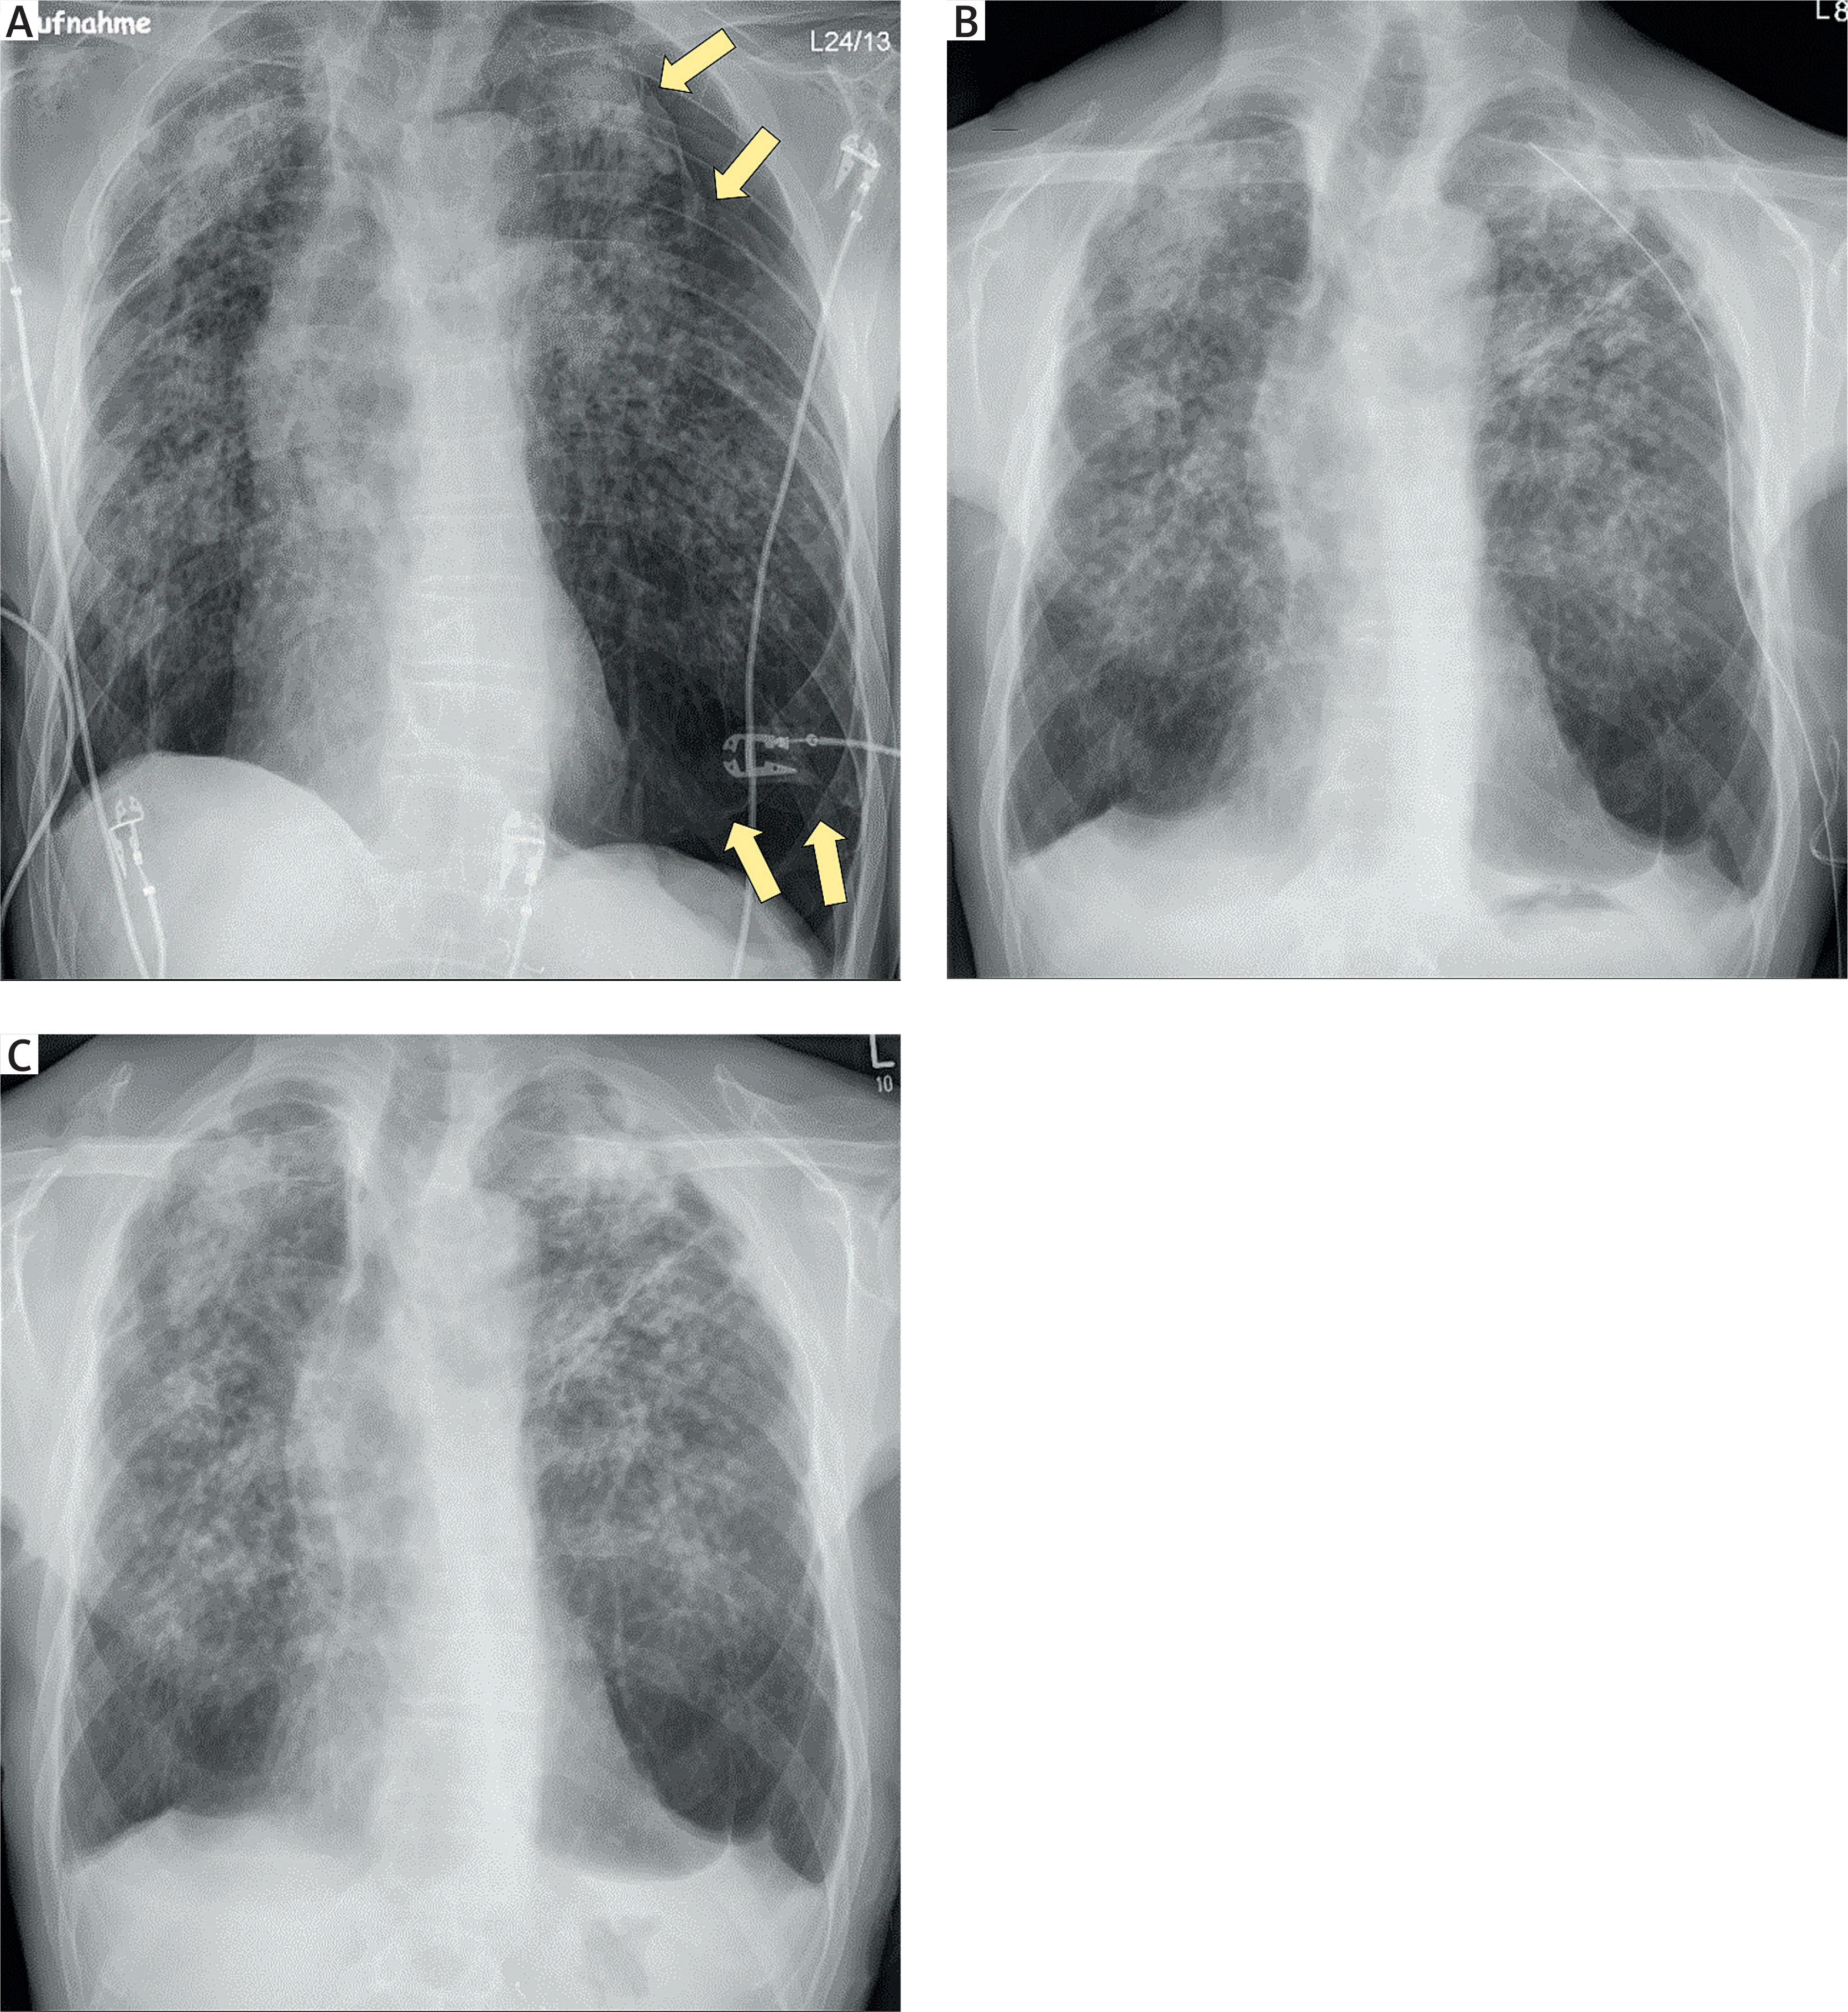

Figure 3

Intraoperative thoracoscopic views showing dense pleuro-pulmonary adhesions (blue arrows) and advanced fibrotic changes of the lung parenchyma: A – dorsoapical region; B – dorsobasal region